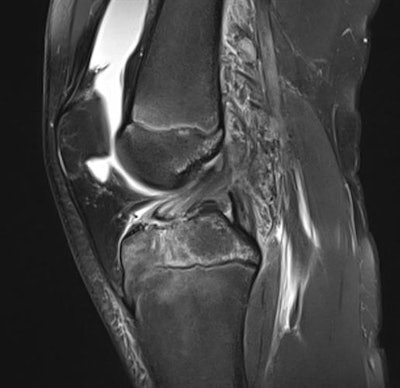

I have worked a lot with hip, knee, and ankle imaging, especially MRI. Injury to the cruciate ligaments, posteromedial and posterolateral corner of the knee has been a special interest, as well as injuries around the ankle. However, the spectrum of sports injuries covers all joints, both upper and lower limb, and every day there is a new challenge and something new to learn.

Imaging can detect both subtle and obvious injuries associated with sporting activity. Early stress reactions in bone, tendons, and soft tissues can be seen, as well as all sorts of ruptures and fractures. However, some injuries are subtle, and if you don't look for them, you will not find them. A sports radiologist must look for smaller changes than other radiologists are used to. This may be because the athlete is imaged very early after an injury or after the start of a complaint, and smaller injuries may be more important in an athlete than in other patients.